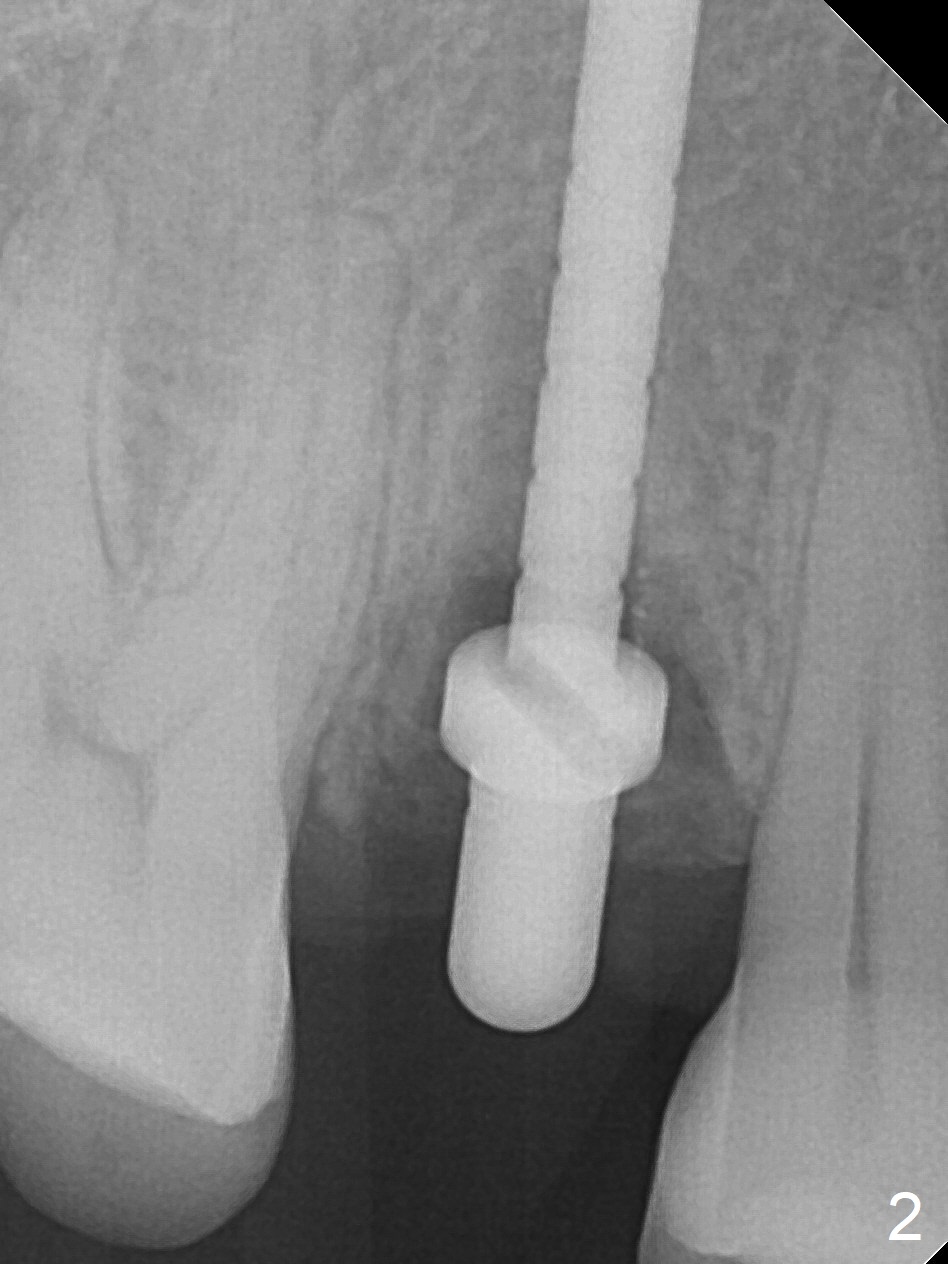

After extraction of residual root at #4 with mesiopalatal subgingival margin (Fig.1), the mesiopalatal crestal bone loss is noted. Instead of the mesial slope, the initial point of the osteotomy is at the mesial and middle (buccopalatally) of the socket bottom (Fig.2, 2'). The initial depth with 2 mm drill is 20 mm (gingival level), while the last drill (3 mm) is used for 17 mm (because of soft bone). When a 3.8x16 mm implant is placed (Fig.3,4), the distal gap of the socket is closed, suggesting that the implant moves to the least resistant area. However, it is favorable to the mesial crestal defect (Fig.4). The buccopalatal position of the abutment (4.5x4(4) mm) is a little too palatal (Fig.5, taken prior to provisional fabrication). The implant seems to have osteointegrated 6 months postop (Fig.6).